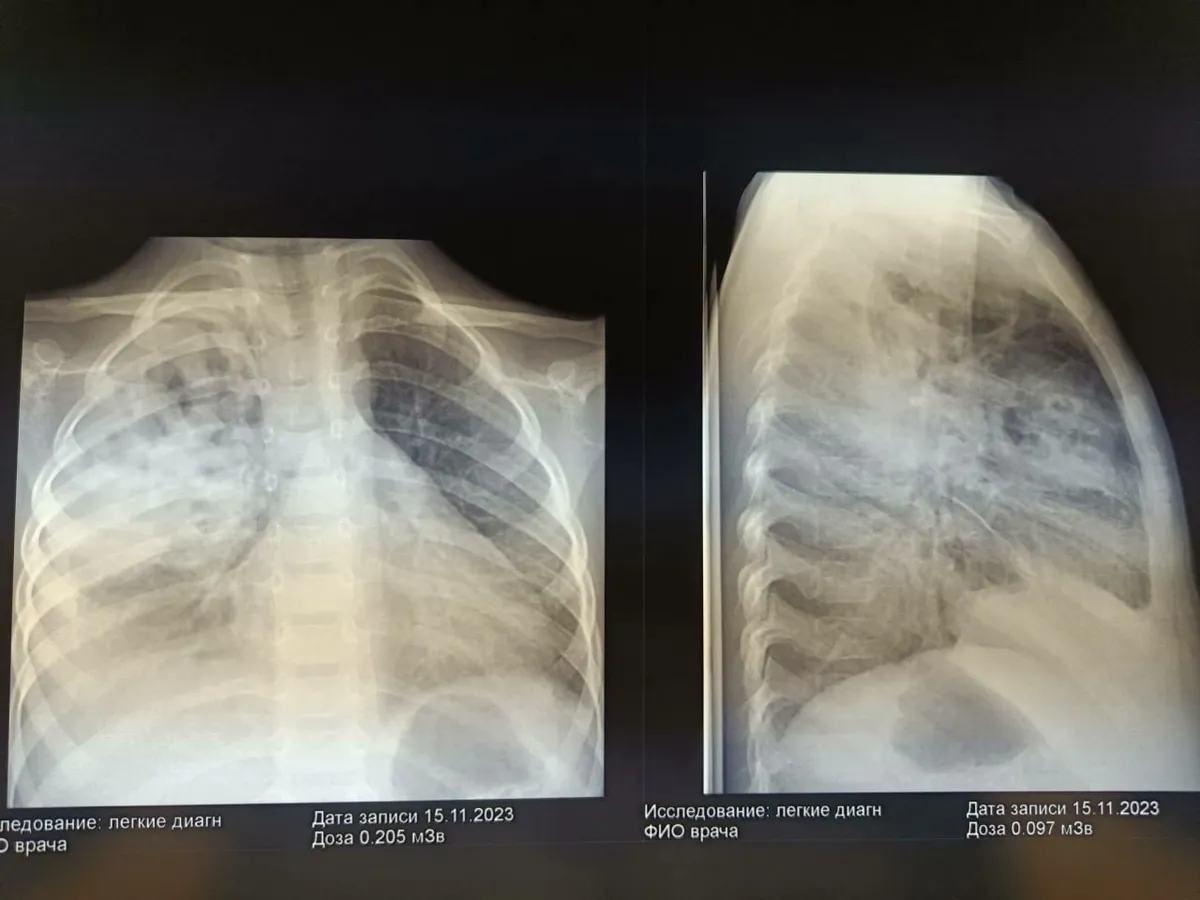

Врачи педиатрического отделения №2 ОДКБ спасли ребенка, страдавшего от тяжелой деструктивной пневмонии с пневмотораксом. Они провели необходимые процедуры, включая дренирование плевральной полости и назначение адекватной антибактериальной терапии, а также физиотерапии, чтобы помочь малышу восстановиться.